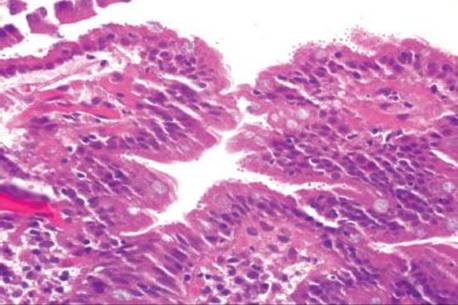

Figure 3.327 Giardiasis. At low power, the duodenal mucosa looks fairly unremarkable, except for the haphazardly arranged luminal debris characteristic of giardiasis. This patient was clinically thought to have an occult malignancy based on the profound weight loss, but all symptoms resolved with Giardiaeradication.

Giardia is the most common intestinal protozoan causing diarrhea in humans (Fig. 3.327).192 Part of the protozoan’s success stems from its ability to infect both the immunocompromised and immunocompetent and its ability to be perpetuated in silent carriers (or asymptomatic patients). This awareness of asymptomatic Giardia infections is important such that one is not misled by a lack of diarrhea&emdash;it happens! Nevertheless, treatment of these asymptomatic cases is critical for prevention of onward spread. The cyst is transmitted via contaminated water or via fecal–oral route, and the flagellated trophozoite adheres to the intestinal epithelium. On duodenal mucosa biopsies, the organisms haphazardly swirl close to the mucosal surface. They can bear such a haphazard arrangement that they can be mistaken for luminal debris to the untrained eye. On closer examination, the trophozoites have been described as clown-faced or pear-shaped based on their peculiar binucleate structure (Figs. 3.328–3.332). Diagnosis can be confirmed with stool smears for the trophozoites or cysts, stool antigen assays, or serologic studies. The only FDA approved treatment is furazolidone (Furoxone),190 although metronidazole is the most common first-line therapy. In the unusual case of recurrent or medically nonresponsive giardiasis, consider the following immunodeficiencies: